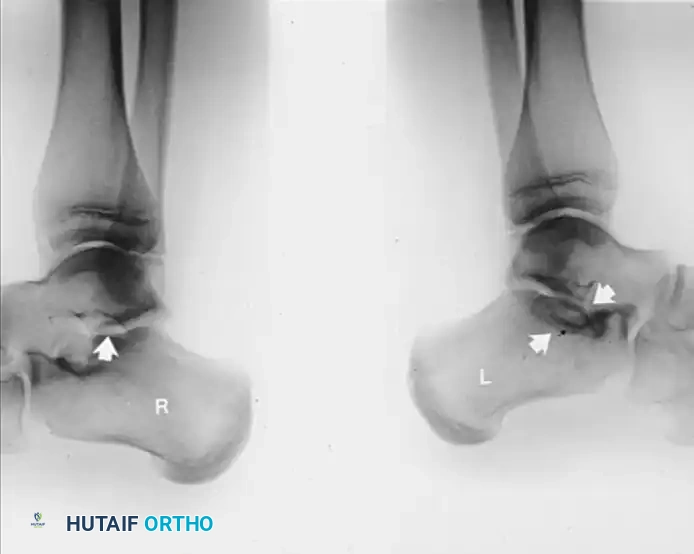

FIGURE 82-79 A: Harris-Beath axial calcaneal (coalition) view utilized to identify middle facet tarsal coalitions. Note the normal middle facet on the right and an incomplete middle facet coalition on the left.

FIGURE 82-79 B: Lateral radiograph of the hindfeet of the same patient. Note the normal middle and posterior facets on the right. On the left, observe the loss of normal “space” at the middle facet, rounding of the lateral process of the talus, and a sclerotic semicircle in the calcaneus inferior to the middle facet, representing the overlap of the cortical margins of the sustentaculum and the bony bar.